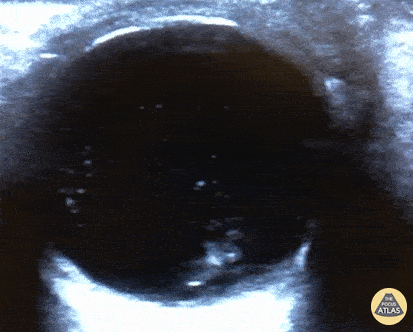

Retinal Detachment. Francisco Norman